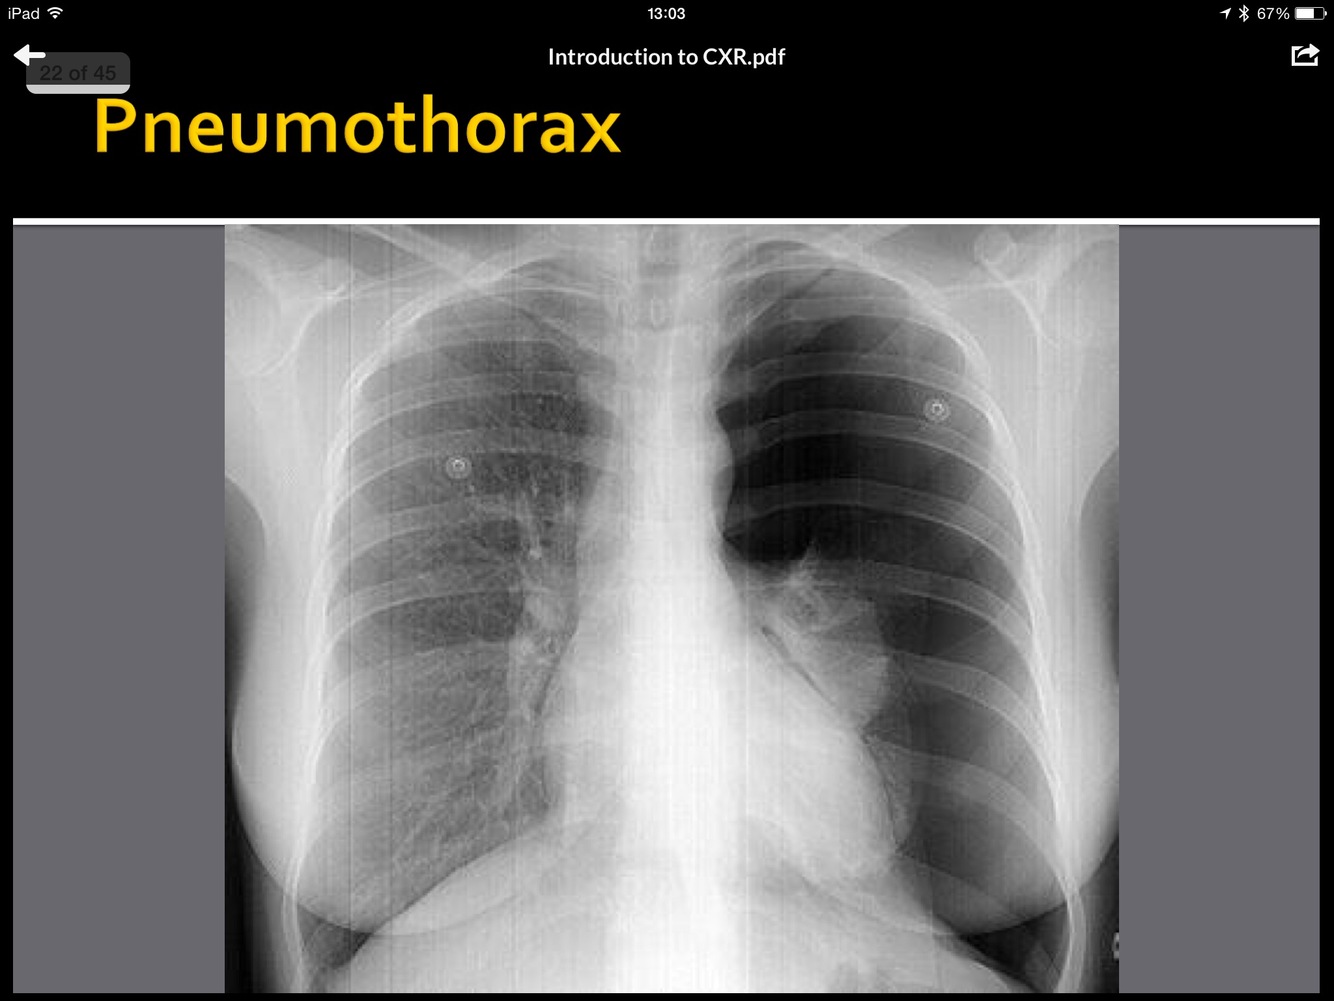

whatis the abnormality?